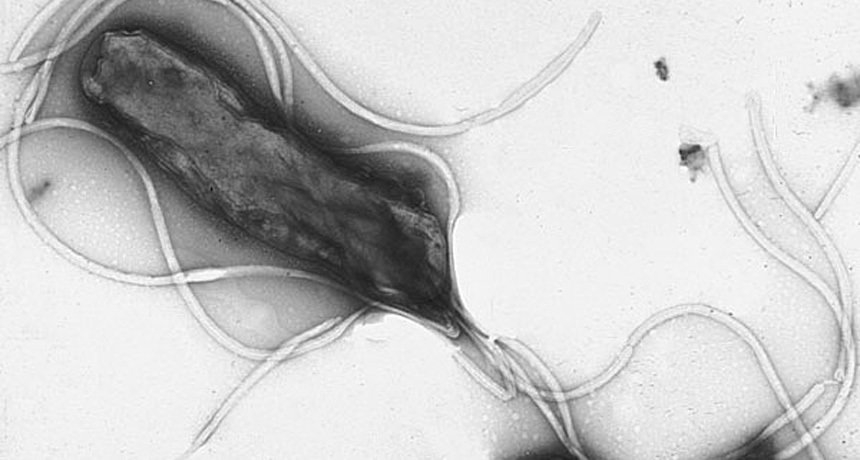

Strains of Helicobacter pylori that do not evolve along with a population may increase individuals' risk for cancer.

Yutaka Tsutsumi/Wikimedia Commons